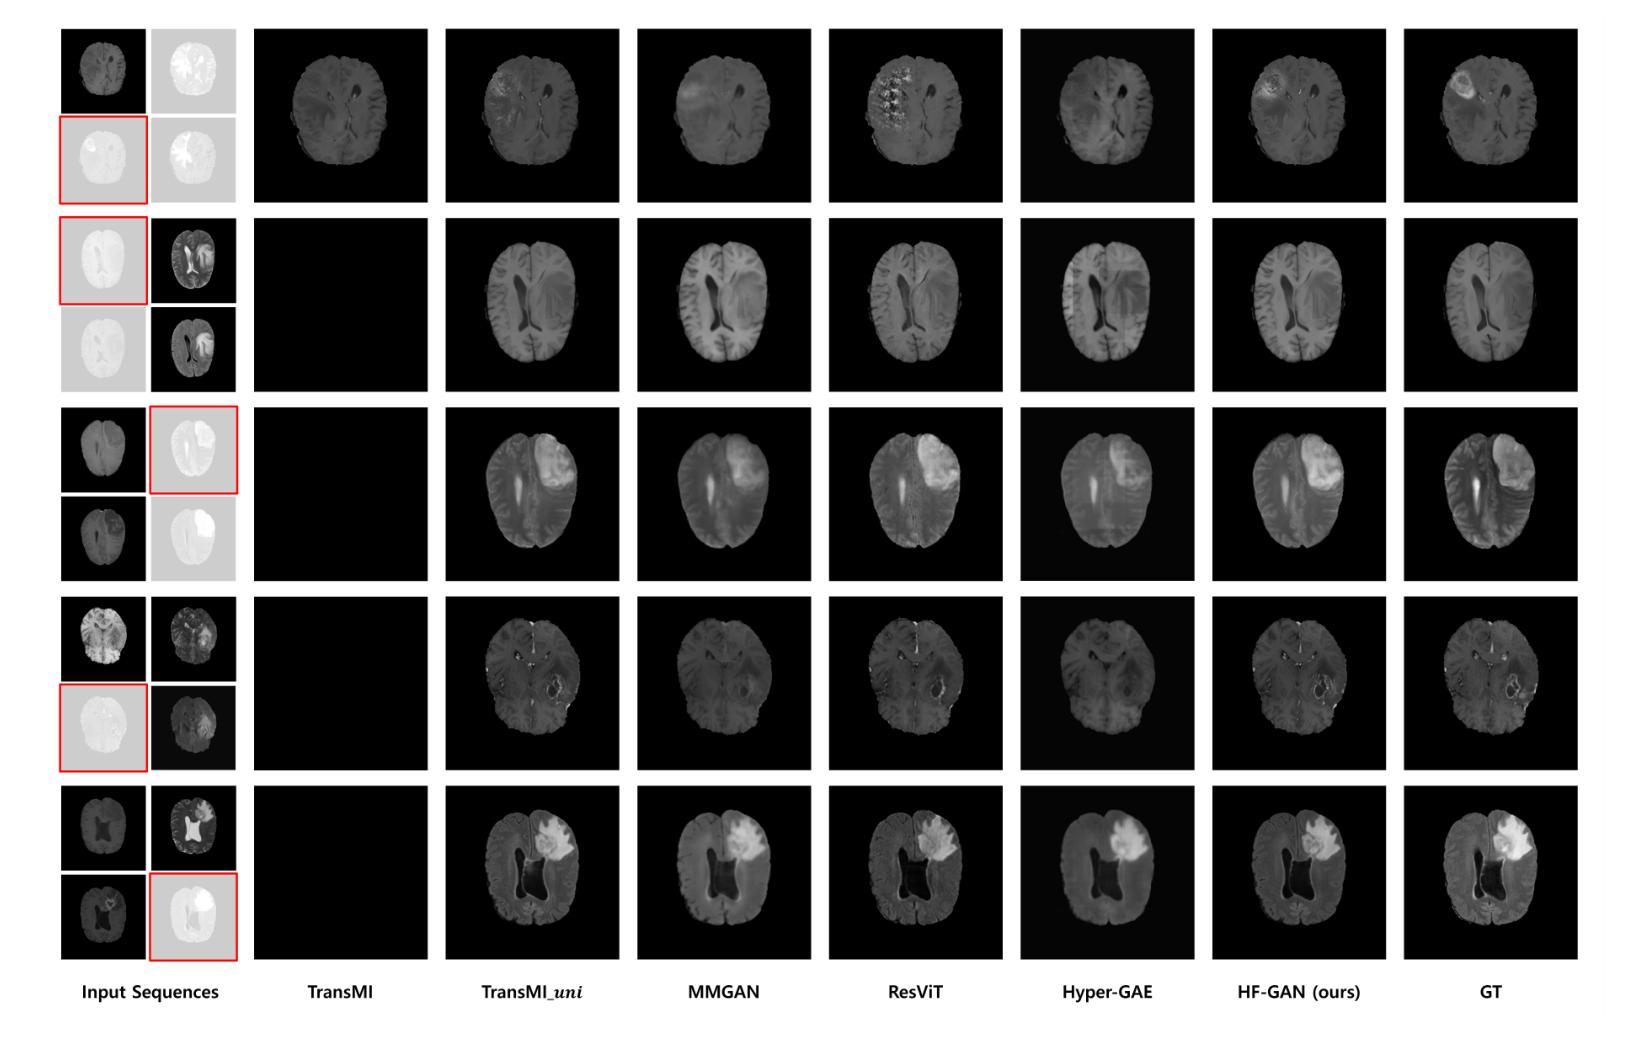

Multisequence Magnetic Resonance Imaging (MRI) provides a more reliable diagnosis in clinical applications through complementary information across sequences. However, in practice, the absence of certain MR sequences is a common problem that can lead to inconsistent analysis results. In this work, we propose a novel unified framework for synthesizing multisequence MR images, called hybrid-fusion GAN (HF-GAN). The fundamental mechanism of this work is principled feature disentanglement, which aligns the design of the architecture with the complexity of the features. A powerful many-to-one stream is constructed for the extraction of complex complementary features, while utilizing parallel, one-to-one streams to process modality-specific information. These disentangled features are dynamically integrated into a common latent space by a channel attention-based fusion module (CAFF) and then transformed via a modality infuser to generate the target sequence. We validated our framework on public datasets of both healthy and pathological brain MRI. Quantitative and qualitative results show that HF-GAN achieves state-of-the-art performance, with our 2D slice-based framework notably outperforming a leading 3D volumetric model. Furthermore, the utilization of HF-GAN for data imputation substantially improves the performance of the downstream brain tumor segmentation task, demonstrating its clinical relevance.

多序列磁共振成像(MRI)通过序列间的互补信息提供更可靠的临床诊断。然而,在实践中,某些MR序列的缺失是一个常见问题,可能导致分析结果不一致。在这项工作中,我们提出了一种合成多序列MR图像的新型统一框架,称为混合融合生成对抗网络(HF-GAN)。这项工作的基本机制是特征解耦,它将架构的设计与特征的复杂性相匹配。我们构建了一个强大的多对一流,用于提取复杂的互补特征,同时利用并行的一对一流来处理特定于模态的信息。这些解耦的特征通过基于通道注意力的融合模块(CAFF)动态地集成到一个公共潜在空间中,然后通过模态注入器进行转换以生成目标序列。我们在公共数据集上对健康和病理性大脑MRI的框架进行了验证。定量和定性结果表明,HF-GAN达到了最先进的技术性能,我们的基于2D切片的框架显著优于领先的3D体积模型。此外,使用HF-GAN进行数据插补大大提高了下游脑肿瘤分割任务的性能,证明了其临床相关性。

本文介绍了一种基于混合融合生成对抗网络(HF-GAN)的多序列磁共振成像(MRI)合成框架。该框架通过特征分解和动态集成技术,利用不同序列的MRI信息,解决了实际应用中某些MR序列缺失导致的不一致分析结果问题。在公共数据集上的验证结果显示,HF-GAN达到了最先进的性能,并在二维切片框架上显著优于领先的的三维体积模型。此外,利用HF-GAN进行数据补全可显著提高下游脑肿瘤分割任务的性能,显示出其临床价值。

4. HF-GAN达到了最先进的性能表现,并在二维切片框架上优于领先的的三维体积模型。